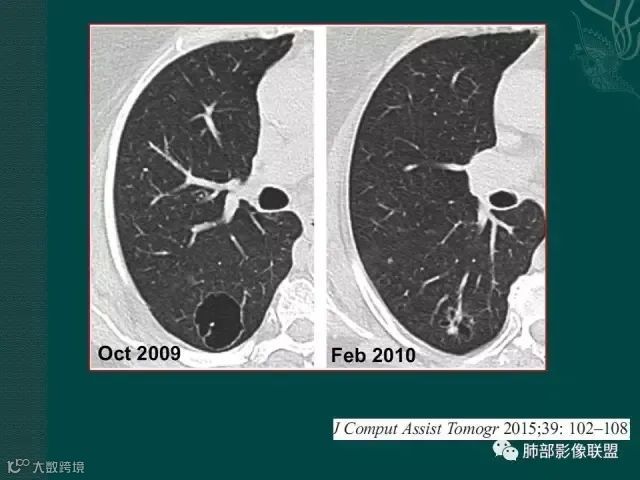

第一个是肺腺癌,边缘有毛刺,多发小空泡,直径不到5mm;